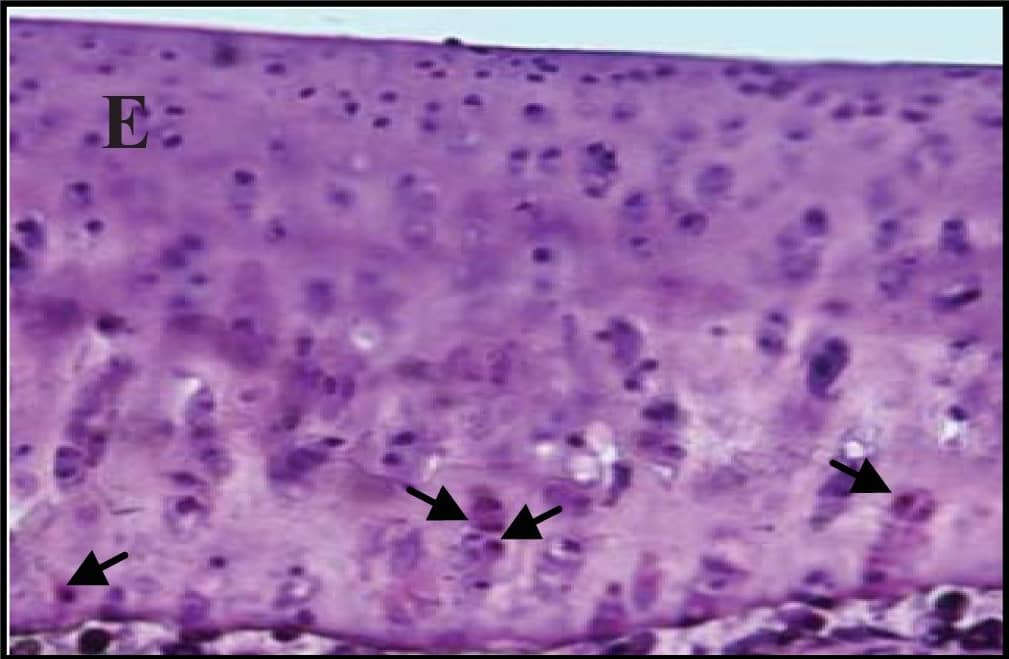

Detection of Mouse Caspase-3 by Immunocytochemistry/Immunofluorescence

Hepatocyte ARNT deletion alters fibrotic and apoptotic gene expression in the TAA model of fibrosis.Results for FC are shown in black columns and LARNT in white columns. Results are expressed relative to FC level. (A) Messenger RNA expression of ARNT and collagen isotypes. (B) Expression of genes regulating fibrosis in FC and LARNT mice. (C) F4/80 and inflammatory cytokine expression in FC and LARNT mice. (D) Apoptotic gene expression in FC and LARNT mice. (E) Representative histology of FC liver stained with anti-Caspase 3 at 100X magnification. (F) Representative histology of LARNT liver stained with anti-Caspase 3 at 100X magnification. (G) Average Caspase 3 positive cell counts per field of view at 100 X magnification. Mean±SEM, * = p<0.05 ** = p<0.01, *** = p<0.001. N = 5-6/group. Image collected and cropped by CiteAb from the following publication (https://dx.plos.org/10.1371/journal.pone.0121650), licensed under a CC-BY license. Not internally tested by R&D Systems.